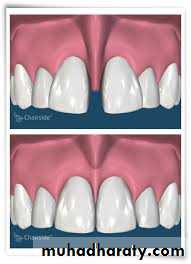

LIP SUPPORT – adequately supported

- unsupported

Contour and appearance of the

vermillion border usually are altered

by tooth loss

Placement of anterior teeth

If the anterior teeth are set too far lingually or palatally, lips will lack the necessary support.

1

Unsupported lip